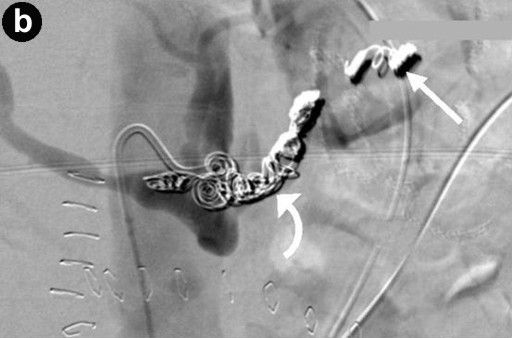

The sites of haemorrhage, management and outcome are summarised in Table 1. All PPH were classified by us as ISGPS type C. The initial CT angiogram revealed the source of the bleeding in all patients and 6 patients went on immediately to have mesenteric angiography. Stent grafting (n=2) was used to control bleeding sites in the common hepatic artery (Figure 1) and coil embolisation (n=5) was employed for bleeding sites arising from branches of superior mesenteric artery, gastroduodenal artery and splenic artery (Figure 2). One patient who underwent metal coil embolisation of proximal hepatic artery for a large psuedoaneurysm from the stump of gastroduodenal artery required further coil packing of the vessel and a follow-up CT scan two weeks after the initial embolisation demonstrated persistent flow in the common hepatic artery. No laparotomy was ever needed after embolization.

Figure 2. a. Axial CT image through the upper abdomen demonstrating a pseudoaneurysm arising from the proximal splenic artery. The splenic artery is compressed by pressure from extravasated blood at the site of the pseudoaneurysm neck (arrowed). b. Digitally subtracted angiographic image from the same patient showing occlusive embolisation coils placed in the splenic artery both distal to ("back door", straight arrow) and proximal to ("front door", curved arrow) the neck of the pseudoaneurysm. The tip of the catheter is in the coeliac trunk. |